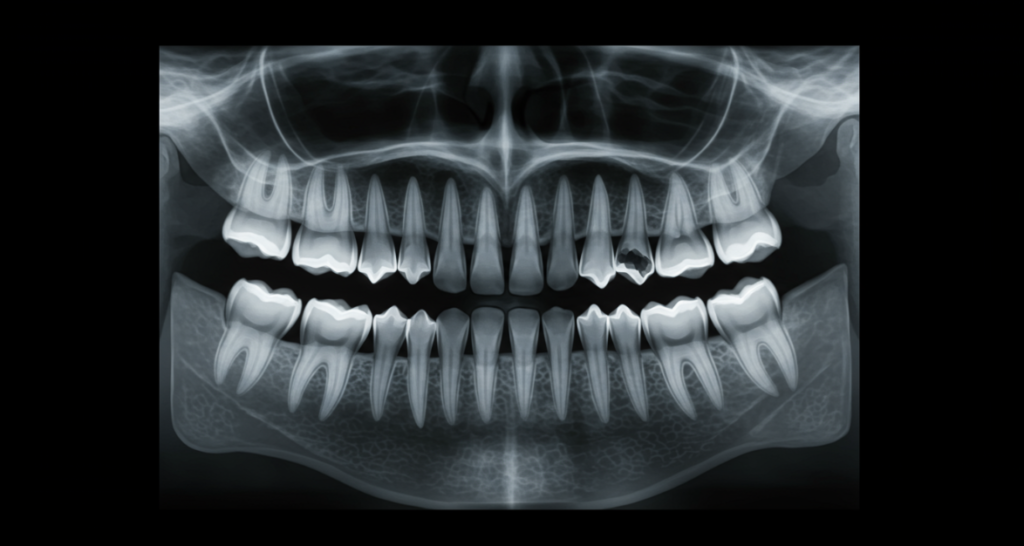

従来のレントゲン撮影は二次元の画像しか得られないため、複雑な根管の形態を完全に把握することは困難でした。しかし、歯科用CTを使用すれば、歯の三次元的な構造を詳細に把握することができます。

- 根管の数や形態を事前に正確に把握できる

- 根の湾曲や分岐を三次元的に確認できる

- 根尖病変(根の先の炎症)の正確な診断が可能

- 治療計画の精度が向上する

特に複雑な根管形態を持つ歯(上顎の大臼歯など)の治療では、CTによる事前診断が成功率を大きく左右します。歯科用CTを導入している医院は、より精密な根管治療が可能と言えるでしょう。